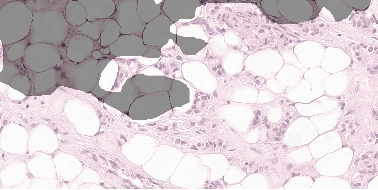

Abstract:Each year, the treatment decisions for more than 230,000 breast cancer patients in the U.S. hinge on whether the cancer has metastasized away from the breast. Metastasis detection is currently performed by pathologists reviewing large expanses of biological tissues. This process is labor intensive and error-prone. We present a framework to automatically detect and localize tumors as small as 100 x 100 pixels in gigapixel microscopy images sized 100,000 x 100,000 pixels. Our method leverages a convolutional neural network (CNN) architecture and obtains state-of-the-art results on the Camelyon16 dataset in the challenging lesion-level tumor detection task. At 8 false positives per image, we detect 92.4% of the tumors, relative to 82.7% by the previous best automated approach. For comparison, a human pathologist attempting exhaustive search achieved 73.2% sensitivity. We achieve image-level AUC scores above 97% on both the Camelyon16 test set and an independent set of 110 slides. In addition, we discover that two slides in the Camelyon16 training set were erroneously labeled normal. Our approach could considerably reduce false negative rates in metastasis detection.